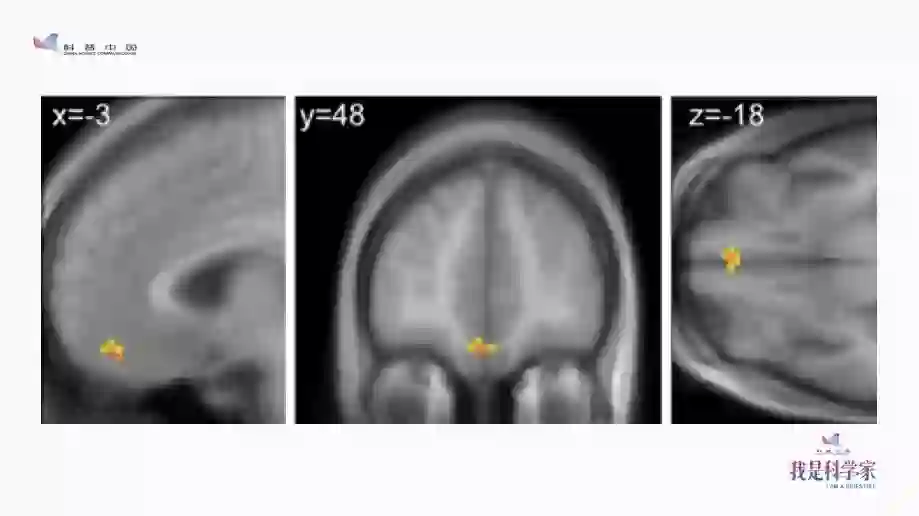

我就去请教那些搞神经科学的哥们儿:我们看到账单的时候,大脑是什么反应?他就给我看了这张图。

图中有个区域叫做Insula(脑岛)。收到账单时,我们的脑岛就会被激活。不只是收到账单,其他时候,比如在赌博中输钱时,逛街看到一个高到离谱的价格标签,我们的脑岛也会被激活——还有什么时候,我们的脑岛会被激活?当我们被人打了一耳光的时候,脑岛也会被激活,因为这个时候很痛,而脑岛也是疼痛中枢的一部分。因此,卡耐基梅隆大学非常有名的经济心理学家George Loewenstein就说过:你收到一份账单,这和打你一巴掌是一样的。所以,支付宝每年年底都会啪啪打我们的脸,太不厚道了。